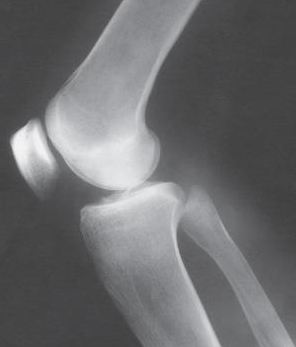

Which knee projection is this

Lateral knee

Patient position for lateral knee is

turned toward affected side, flexed, brought forward

Femoral epicondyles and patella are what to the IR during lateral knee

perpendicular

CR angle in lateral knee is

5 to 7 degrees cephalic

CR enters where for a lateral knee

knee joint 1 inch distal to medial femoral epicondyle

Open patellofemoral joint space seen in

For lateral knee, over rotation results in

less superimposition

For lateral knee, under rotation results in

more superimposition